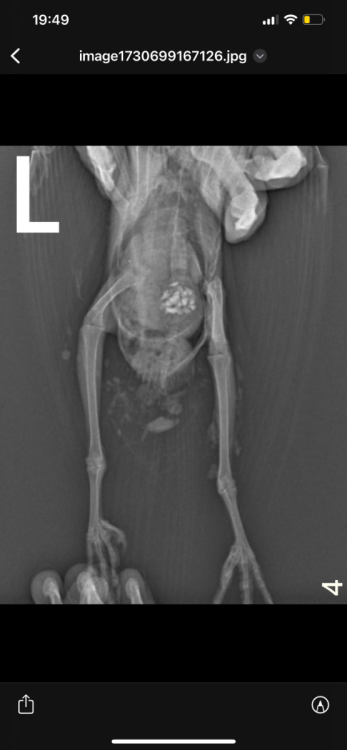

Здравствуйте, неделю назад возле автомобиля обнаружила голубя , лежал на левом боку и не мог встать. Я подумала что сбила машина, взяла его к себе. Съездили к орнитологу , он пощупал лапки , сказал возможно это связано с нервной системой , либо повреждена левая лапа. Голубь, взлетает без проблем. Но не упирается на лапы , теряет координацию и падает + постоянно вся попа в 💩. Кушает хорошо и пьет водичку самостоятельно. Сегодня смотрю , упирается на правую лапу , а левую вытягивает прямо назад.

На всякий случай купила витамины, добавляю по капельки в водичку. Голову не запрокидывает.  Фото рентгена прилагаю. Кто сталкивался с подобным ? Что может быть ?

Возможно есть повреждение бедренной кости- выбита или перелом головки.